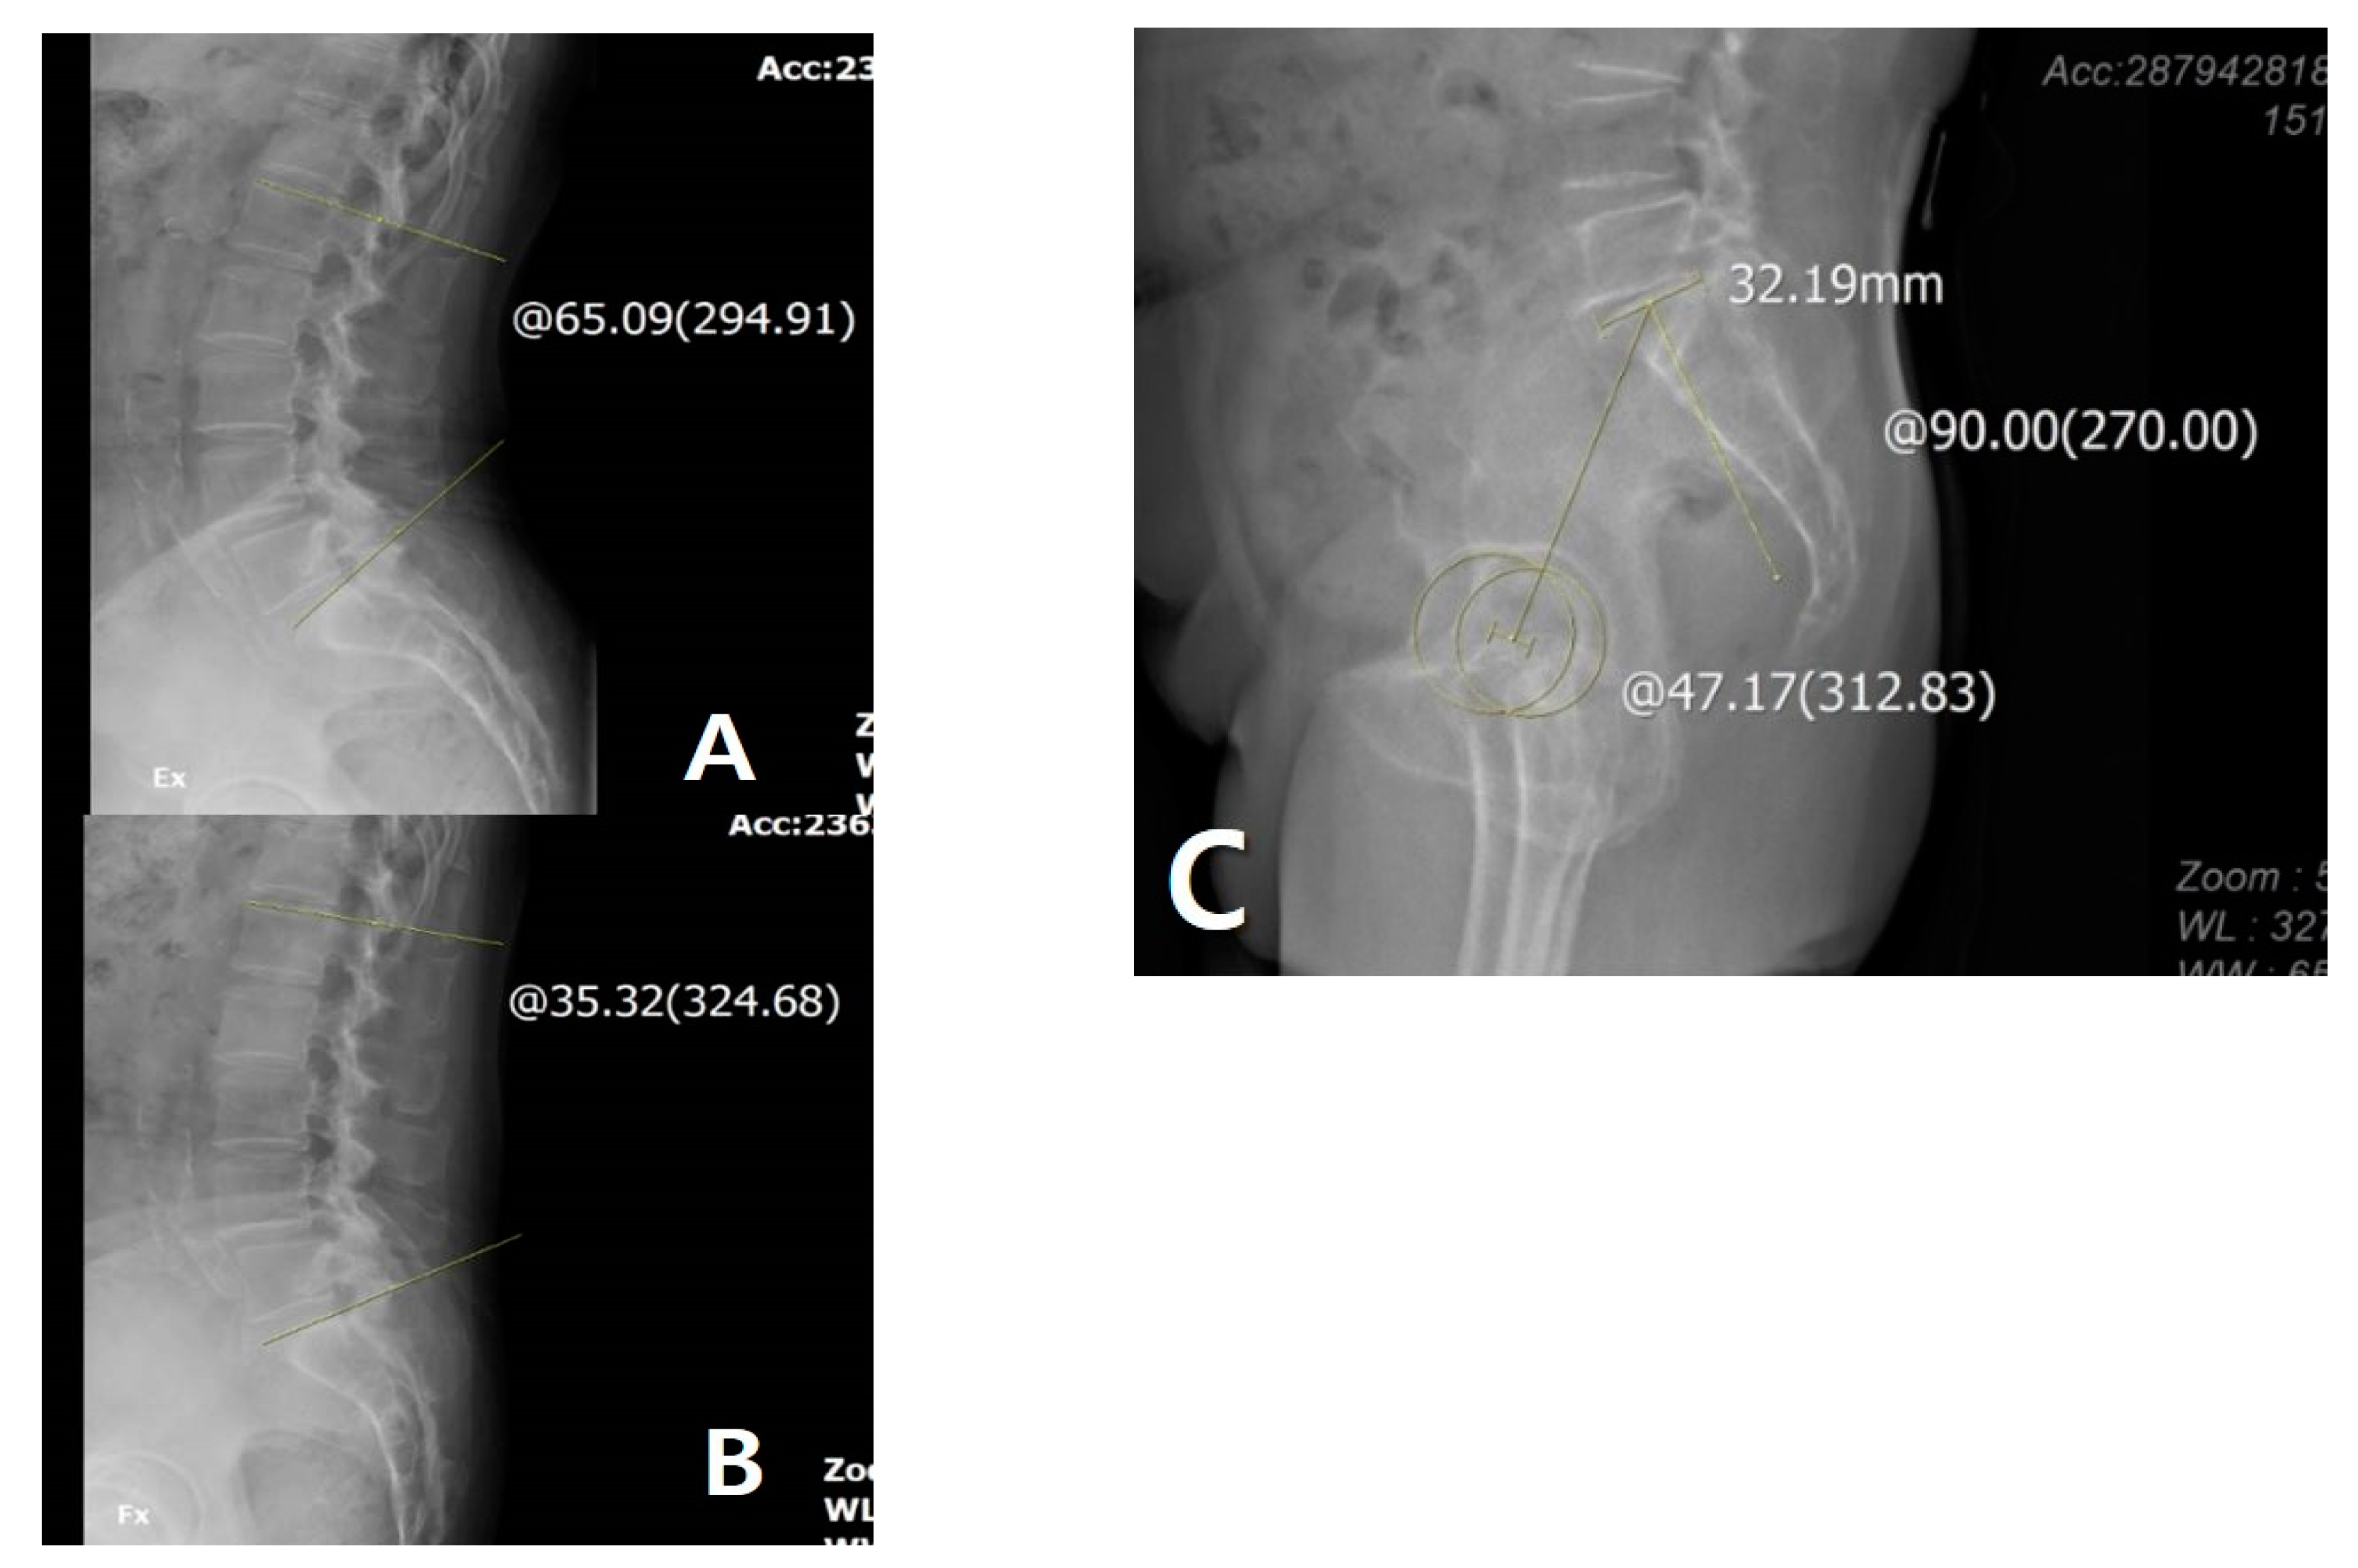

2.2. Changes in Sagittal Alignment after TKA Considering Lumbosacral Flexibility

2.3. Disparity after TKA Considering Lumbosacral Flexibility